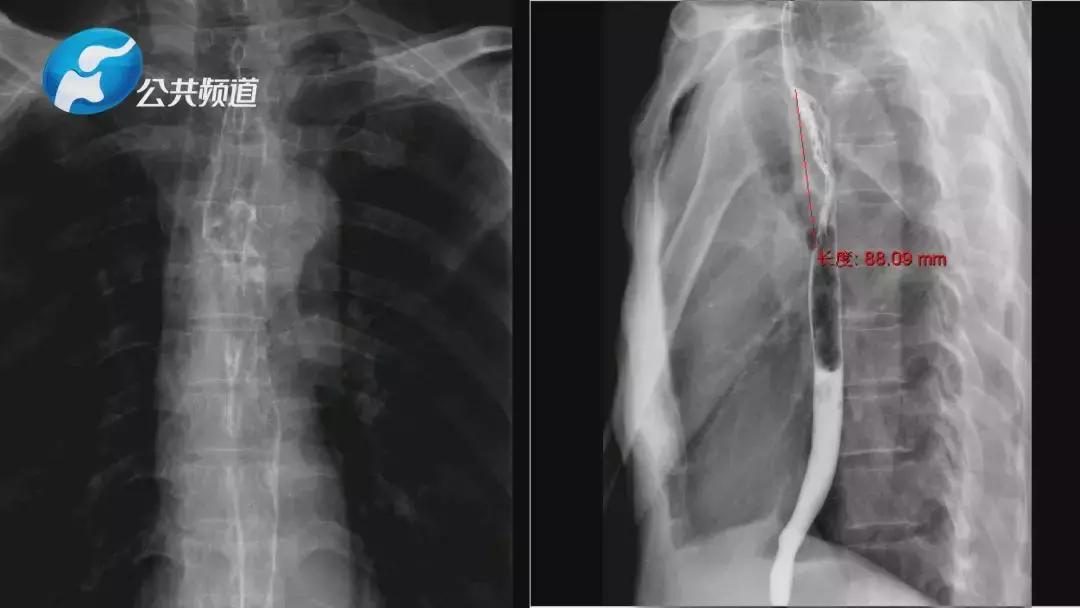

术后第五天,通过上消化道造影检查,患者术后吻合口通畅,形态良好;术后第六天,患者可以经口进流食及半流食;6月26日术后一周,患者开始正常饮食。